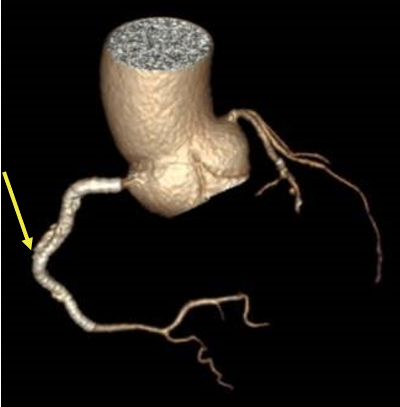

A 73-year-old man was hospitalized due to acute coronary syndrome. Right coronary artery angiography revealed a severely tortuous vessel with long critical stenosis (Figure 1).

Coronary angioplasty was performed by first advancing a Sion guidewire (Asahi), followed by a Launcher Amplatz right 6F guide catheter (Medtronic) with a 2.5 x 15-mm semicompliant balloon. Next, a 3 x 48-mm everolimus-eluting stent was advanced with a GuideLiner 6F extension catheter (Teleflex). After inflation, the stent failed to expand as a result of perforation of the drug-eluting balloon (Figure 2); only partial opening of the ends of the stent was observed, with consequent entrapment of the stent and balloon. Traction proved unsuccessful for retrieval of the device and the balloon hypotube shaft was torn; consequently, the device was lost in the right coronary artery.